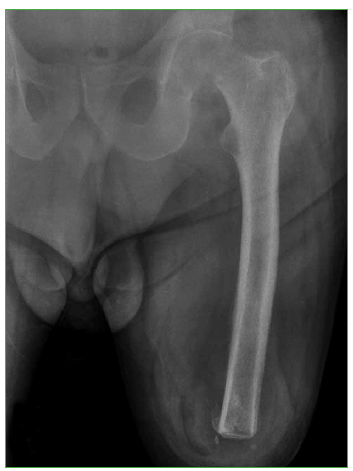

Figura 2.

Radiografía anteroposterior posoperatoria satisfactoria.

Bajo anestesia raquídea, el paciente fue colocado en decúbito lateral derecho. Se realizó una artroplastia total de cadera cementada mediante el abordaje de Gibson modificado y se colocó un clavo de Steinmann en el trocánter mayor para facilitar la dislocación/colocación y controlar la rotación del muñón. La artroplastia incluyó un implante femoral tipo Charnley con componente cefálico de 28 mm y cotilo Muller de 28 mm x 42 mm (Figura 2). En el posoperatorio, se administró profilaxis antibiótica por 48 h y terapia antitrombótica durante 15 días para prevenir complicaciones infecciosas y tromboembólicas.